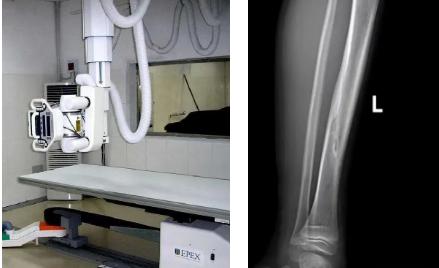

一般骨科創(chuàng)傷的病人,只要到影像科拍一張X光片,很快就會明確診斷有沒有骨折。然而有一些特殊類型骨折的病人,由于拍片影像重疊的緣故,或者骨折未發(fā)生明顯移位,病變可能顯示不出來,等過了一段時間后,骨折部位才能夠顯示清楚。這種類型的骨折,叫做隱匿性骨折。若在臨床上診斷及時且明確,及時固定患者的骨折部位,進行適當治療并減少運動,對患者的恢復(fù)有重要意義。

1.定期復(fù)查。一般于骨折后2-4周,骨折進入骨痂期,骨折斷端有新生骨形成,呈明顯高密度,無論是X線或是CT,都能比較清晰觀察到,通過前后圖像對比,較容易診斷隱匿性骨折。